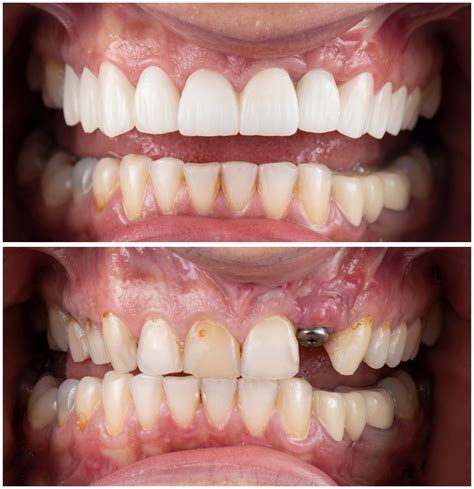

- Mejora de la estética dental: Contribuye a una sonrisa más atractiva y a una mayor confianza en uno mismo.

- Alternativa a las dentaduras postizas: Ofrece una solución más cómoda, estable y duradera.

Ejemplo de una sonrisa restaurada con implantes dentales.